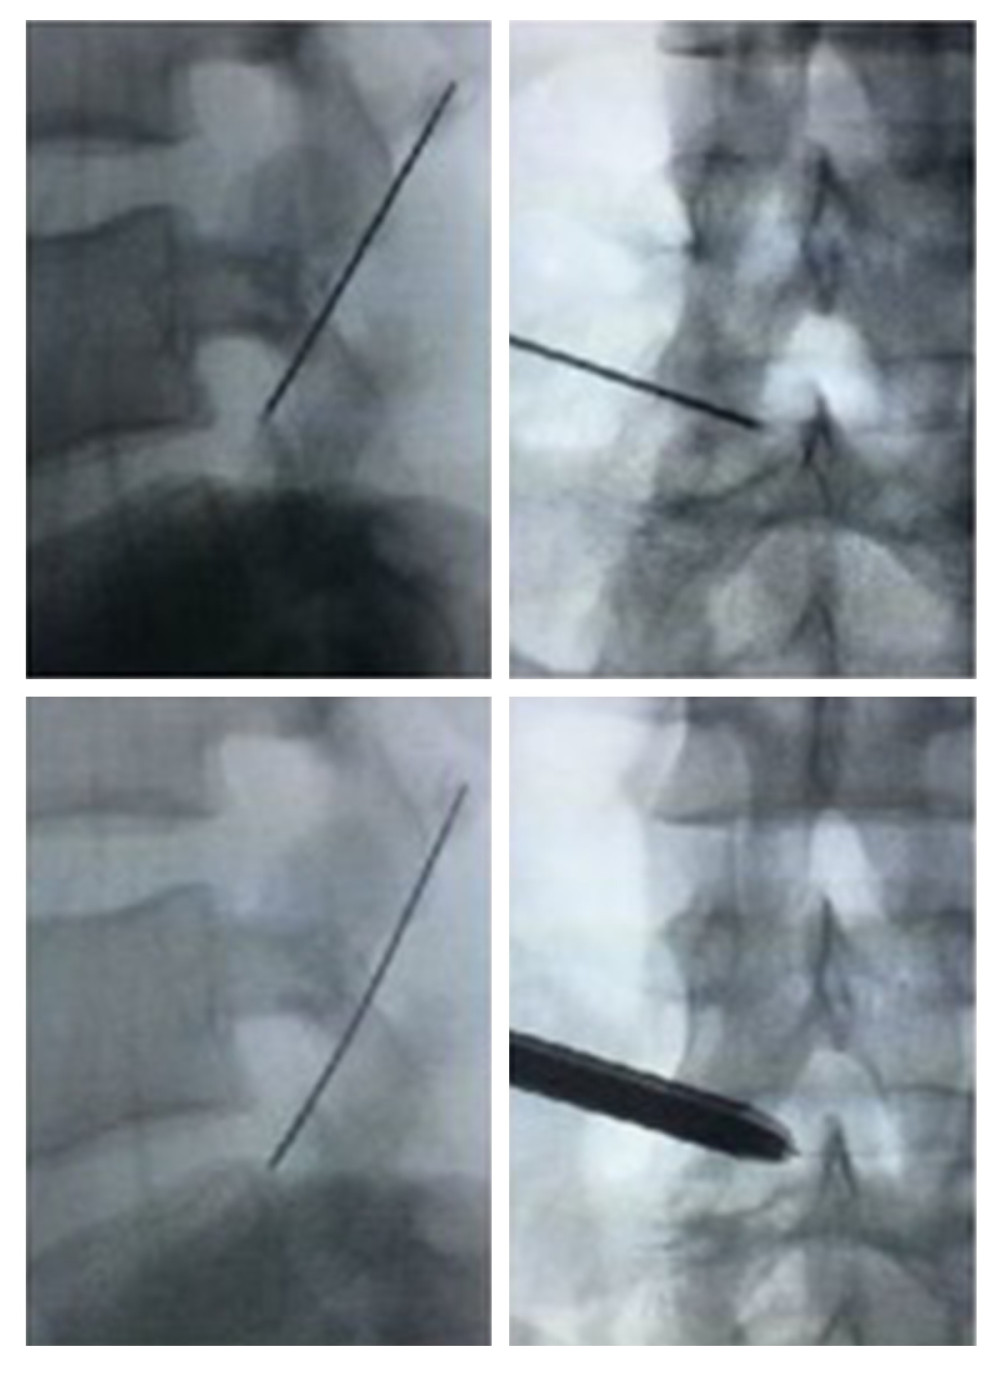

From www.researchgate.net

(PDF) Application of Musculoskeletal Ultrasound Guidance in Lumbar Endoscopic Catheterization Web endoscopic retrograde cholangiopancreatography (ercp) is considered the first line intervention for. Web ct is used to determine the indications for endoscopic us bd, which include the type of biliary obstruction, collateral vessels in the puncture route, ascites, the volume of the liver segment, the distribution of an intrahepatic tumor, and gi tract patency. It can help diagnose and treat.. Endoscopic Catheterization.

From medscimonit.com

Medical Science Monitor Application of Musculoskeletal Ultrasound Endoscopic Catheterization It can help diagnose and treat. Web endoscopic retrograde cholangiopancreatography (ercp) is considered the first line intervention for. Web ct is used to determine the indications for endoscopic us bd, which include the type of biliary obstruction, collateral vessels in the puncture route, ascites, the volume of the liver segment, the distribution of an intrahepatic tumor, and gi tract patency.. Endoscopic Catheterization.